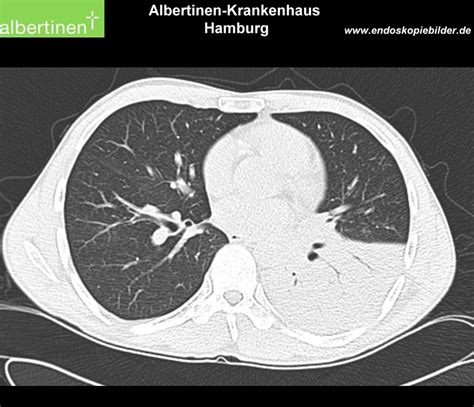

Understand why a pneumonia CT scan is essential for accurate diagnosis. This guide explains how high-resolution imaging detects lung inflammation, identifies complications, and helps doctors determine the severity of infection. Learn what to expect during your chest scan and how this vital diagnostic tool ensures effective treatment for patients with persistent respiratory symptoms.

TitleCT-scan: Lobar pneumonia - DocCheck